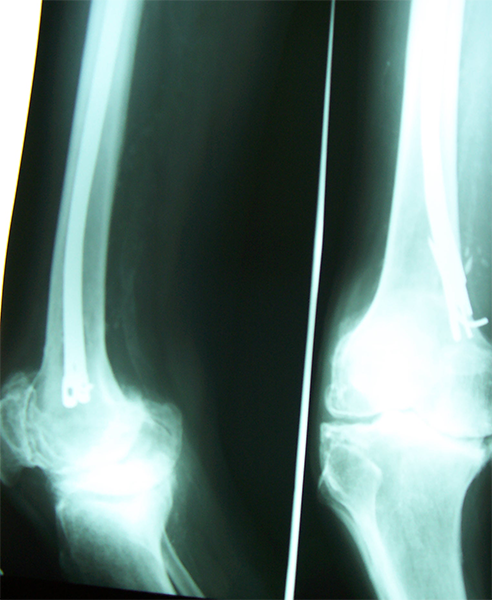

Case:3 Hoffa's Fracture

Pre-Op

Per-Op

Post-Op